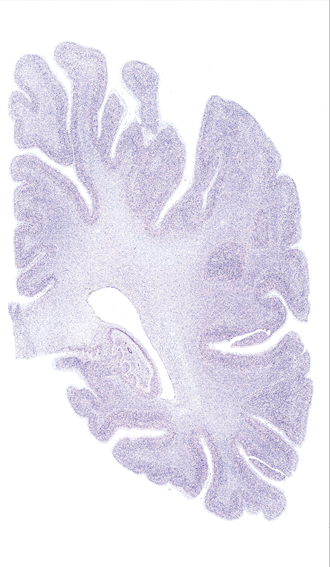

Hi-Resolution Sections · Cells (Nissl Staining) · Virtual Microscopy

Frontal sections (Nissl) from the Atlas Brain:

Slice ID:

r4-0220

Plate NR:

52

Position:

42,7 mm